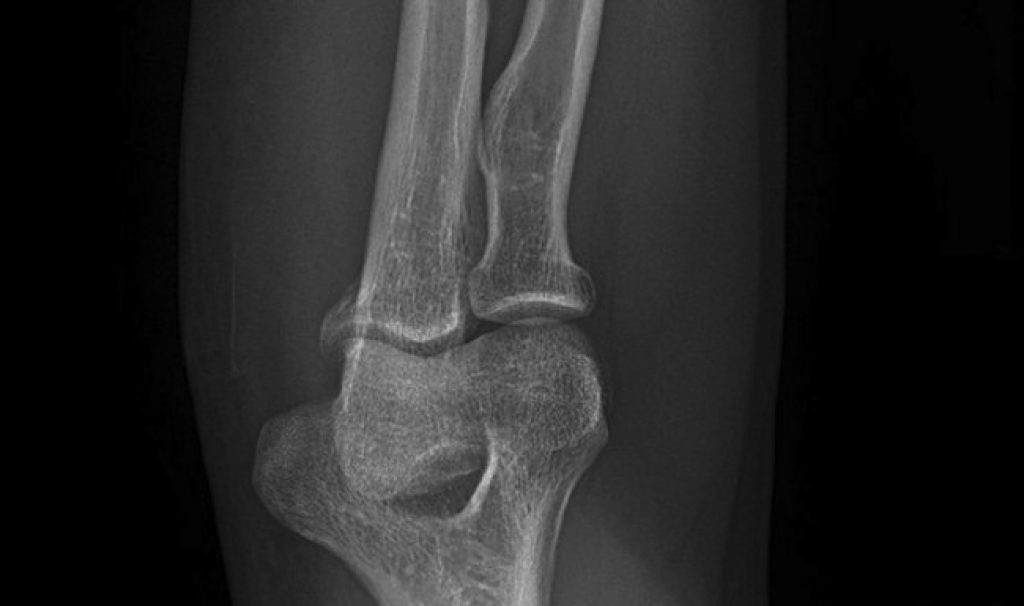

Bone replacement is crucial for treating various conditions when bones cannot self-repair. These include severe breaks, bone cancer and degenerative diseases such as osteoporosis.

Rattan bones could be especially important for replacing large chunks of bone—three centimetres or more—for which existing bone substitutes are unsuitable, the team found. In time, rattan grafts are replaced with newly formed bone without needing further surgery, making it a cheaper and less-invasive choice for long-term treatment, the researchers say.